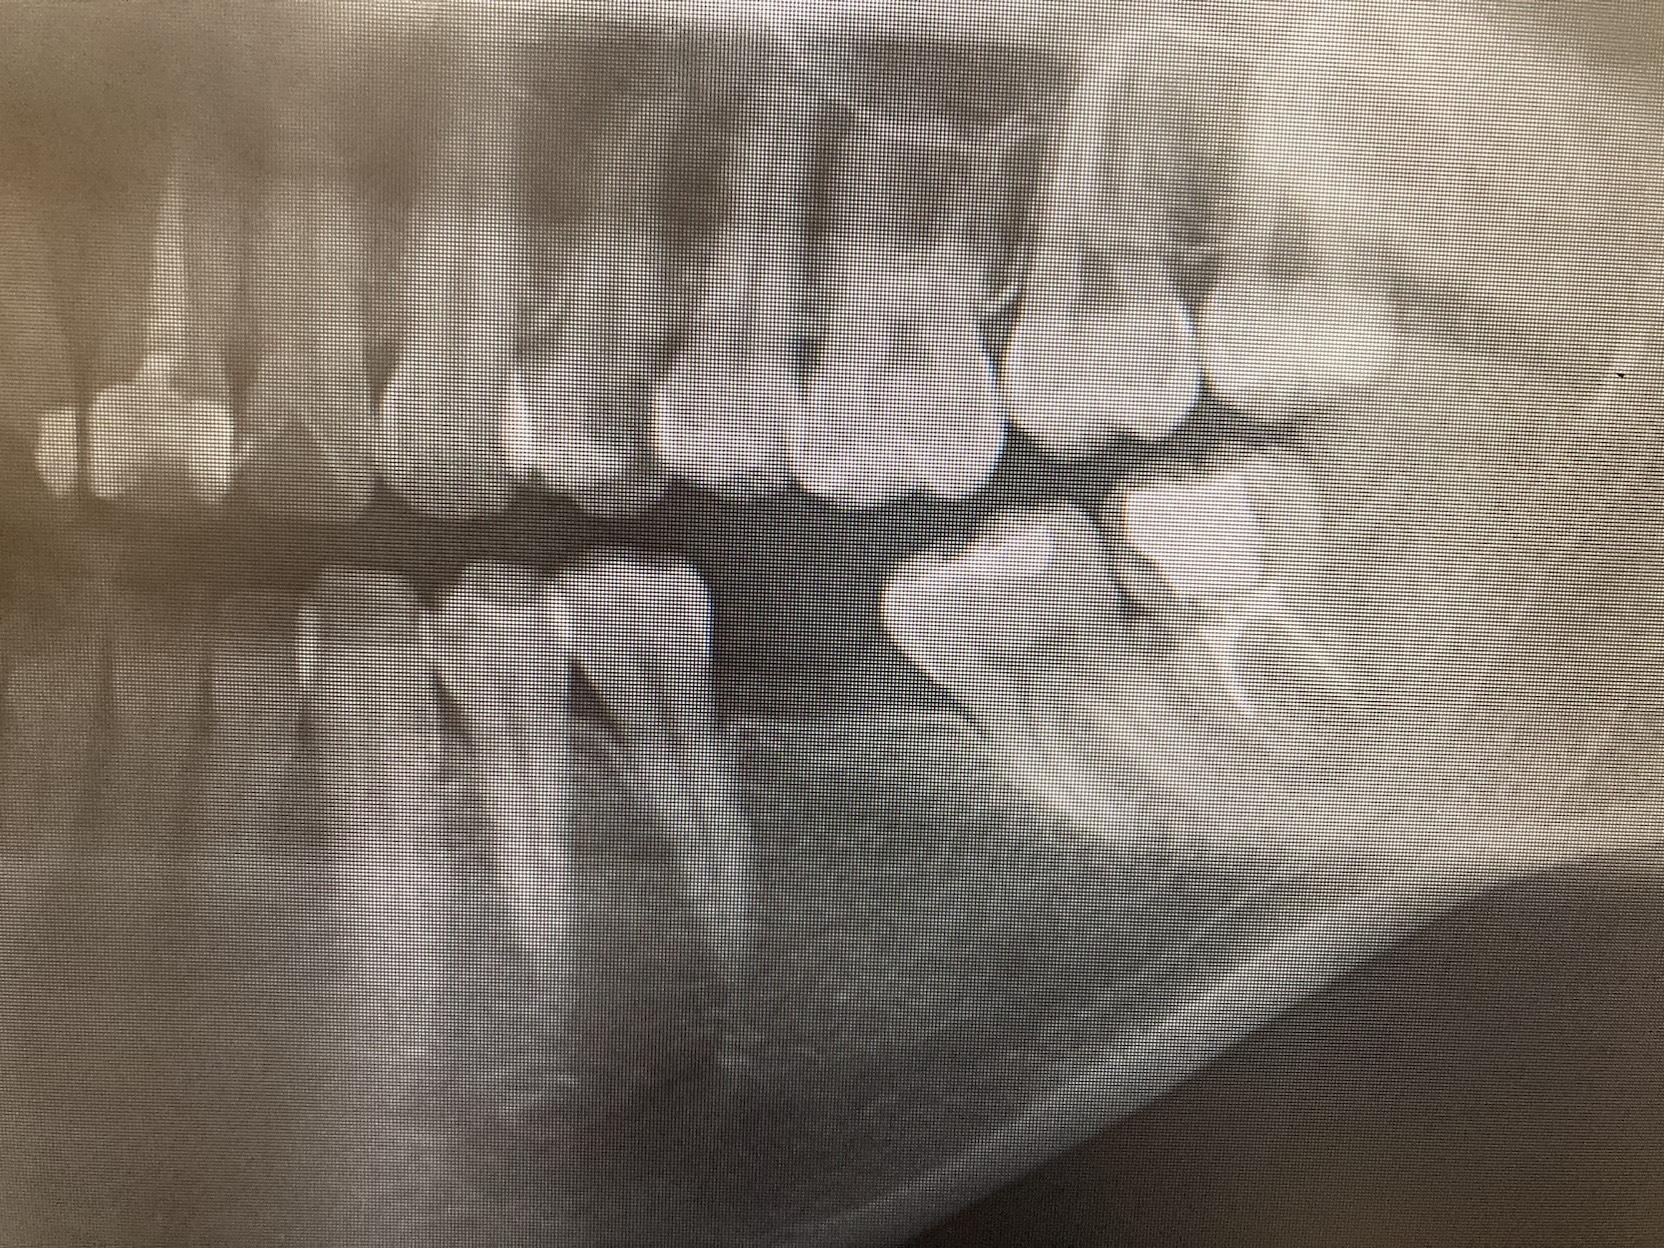

CASE 07

BEFORE

50代。 「噛んだ時に違和感がある」「疲れると歯茎が浮くような感じがする」とのことでご来院。 レントゲン撮影の結果、過去に治療した歯の根の先に細菌が繁殖し、大きな炎症(黒い影)ができている「根尖性歯周炎」の状態でした。